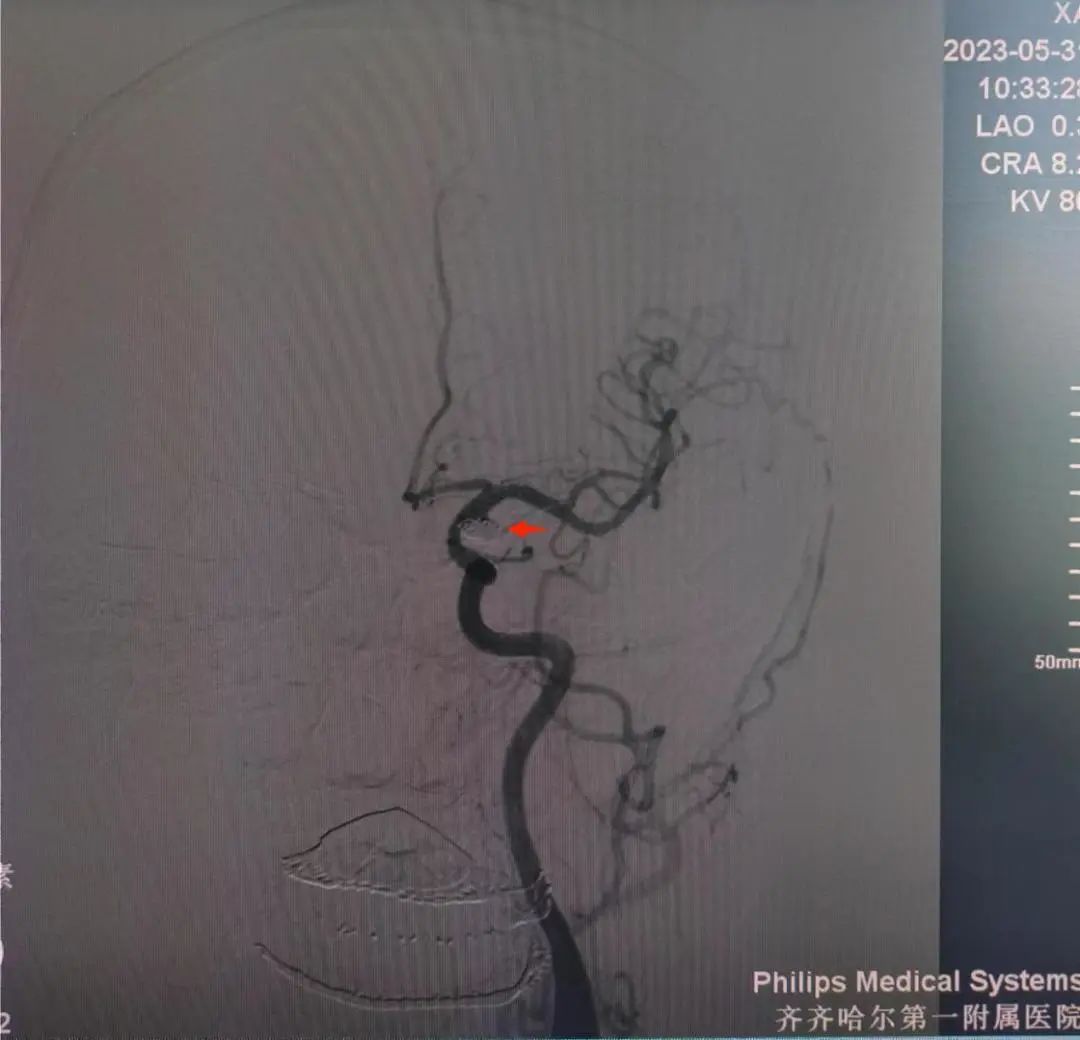

介入手术前后动脉瘤对比

入院后王先生行相关术前检查及准备后行经桡动脉穿刺全脑血管造影,术程顺利。造影结果显示患者动脉瘤栓塞确切动脉瘤体不显影瘤颈无残留,载瘤动脉通畅,这意味着患者的动脉瘤手术极度成功,王先生自己走回病房,他感叹附属一院是咱家乡的好医院,附属一院的医生是咱值得信赖的好医生啊!

造影显示手术成功